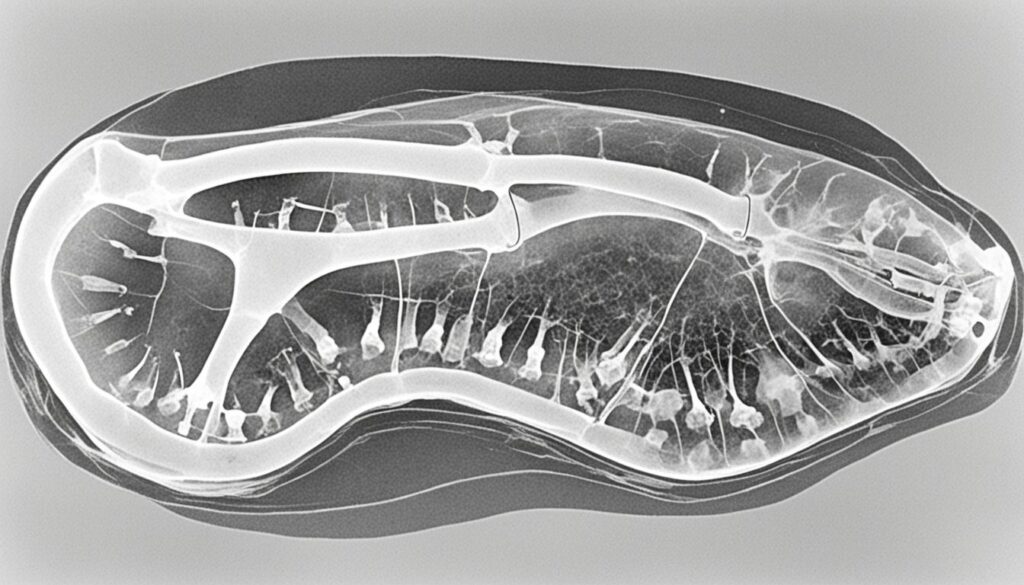

The exact cause of hypertrophic osteopathy in dogs is still unknown, but it is believed to involve reduced vascularity in the periosteum. Clinical signs of this condition may include lameness, long bone pain, and symptoms secondary to the underlying masses. Radiographic imaging, such as X-rays, can reveal the primary masses and peripheral bone reactions.

To confirm the diagnosis of hypertrophic osteopathy, radiographic imaging such as X-rays is essential. This imaging technique allows veterinarians to visualize the characteristic bilateral and symmetrical changes primarily along the long bones. Detecting these changes early is vital for identifying and treating the underlying disease effectively.

Radiographic images provide valuable insights into the extent of bone reactions and the presence of underlying masses. These images help veterinarians determine the appropriate treatment plan and monitor the progression of the disease over time.